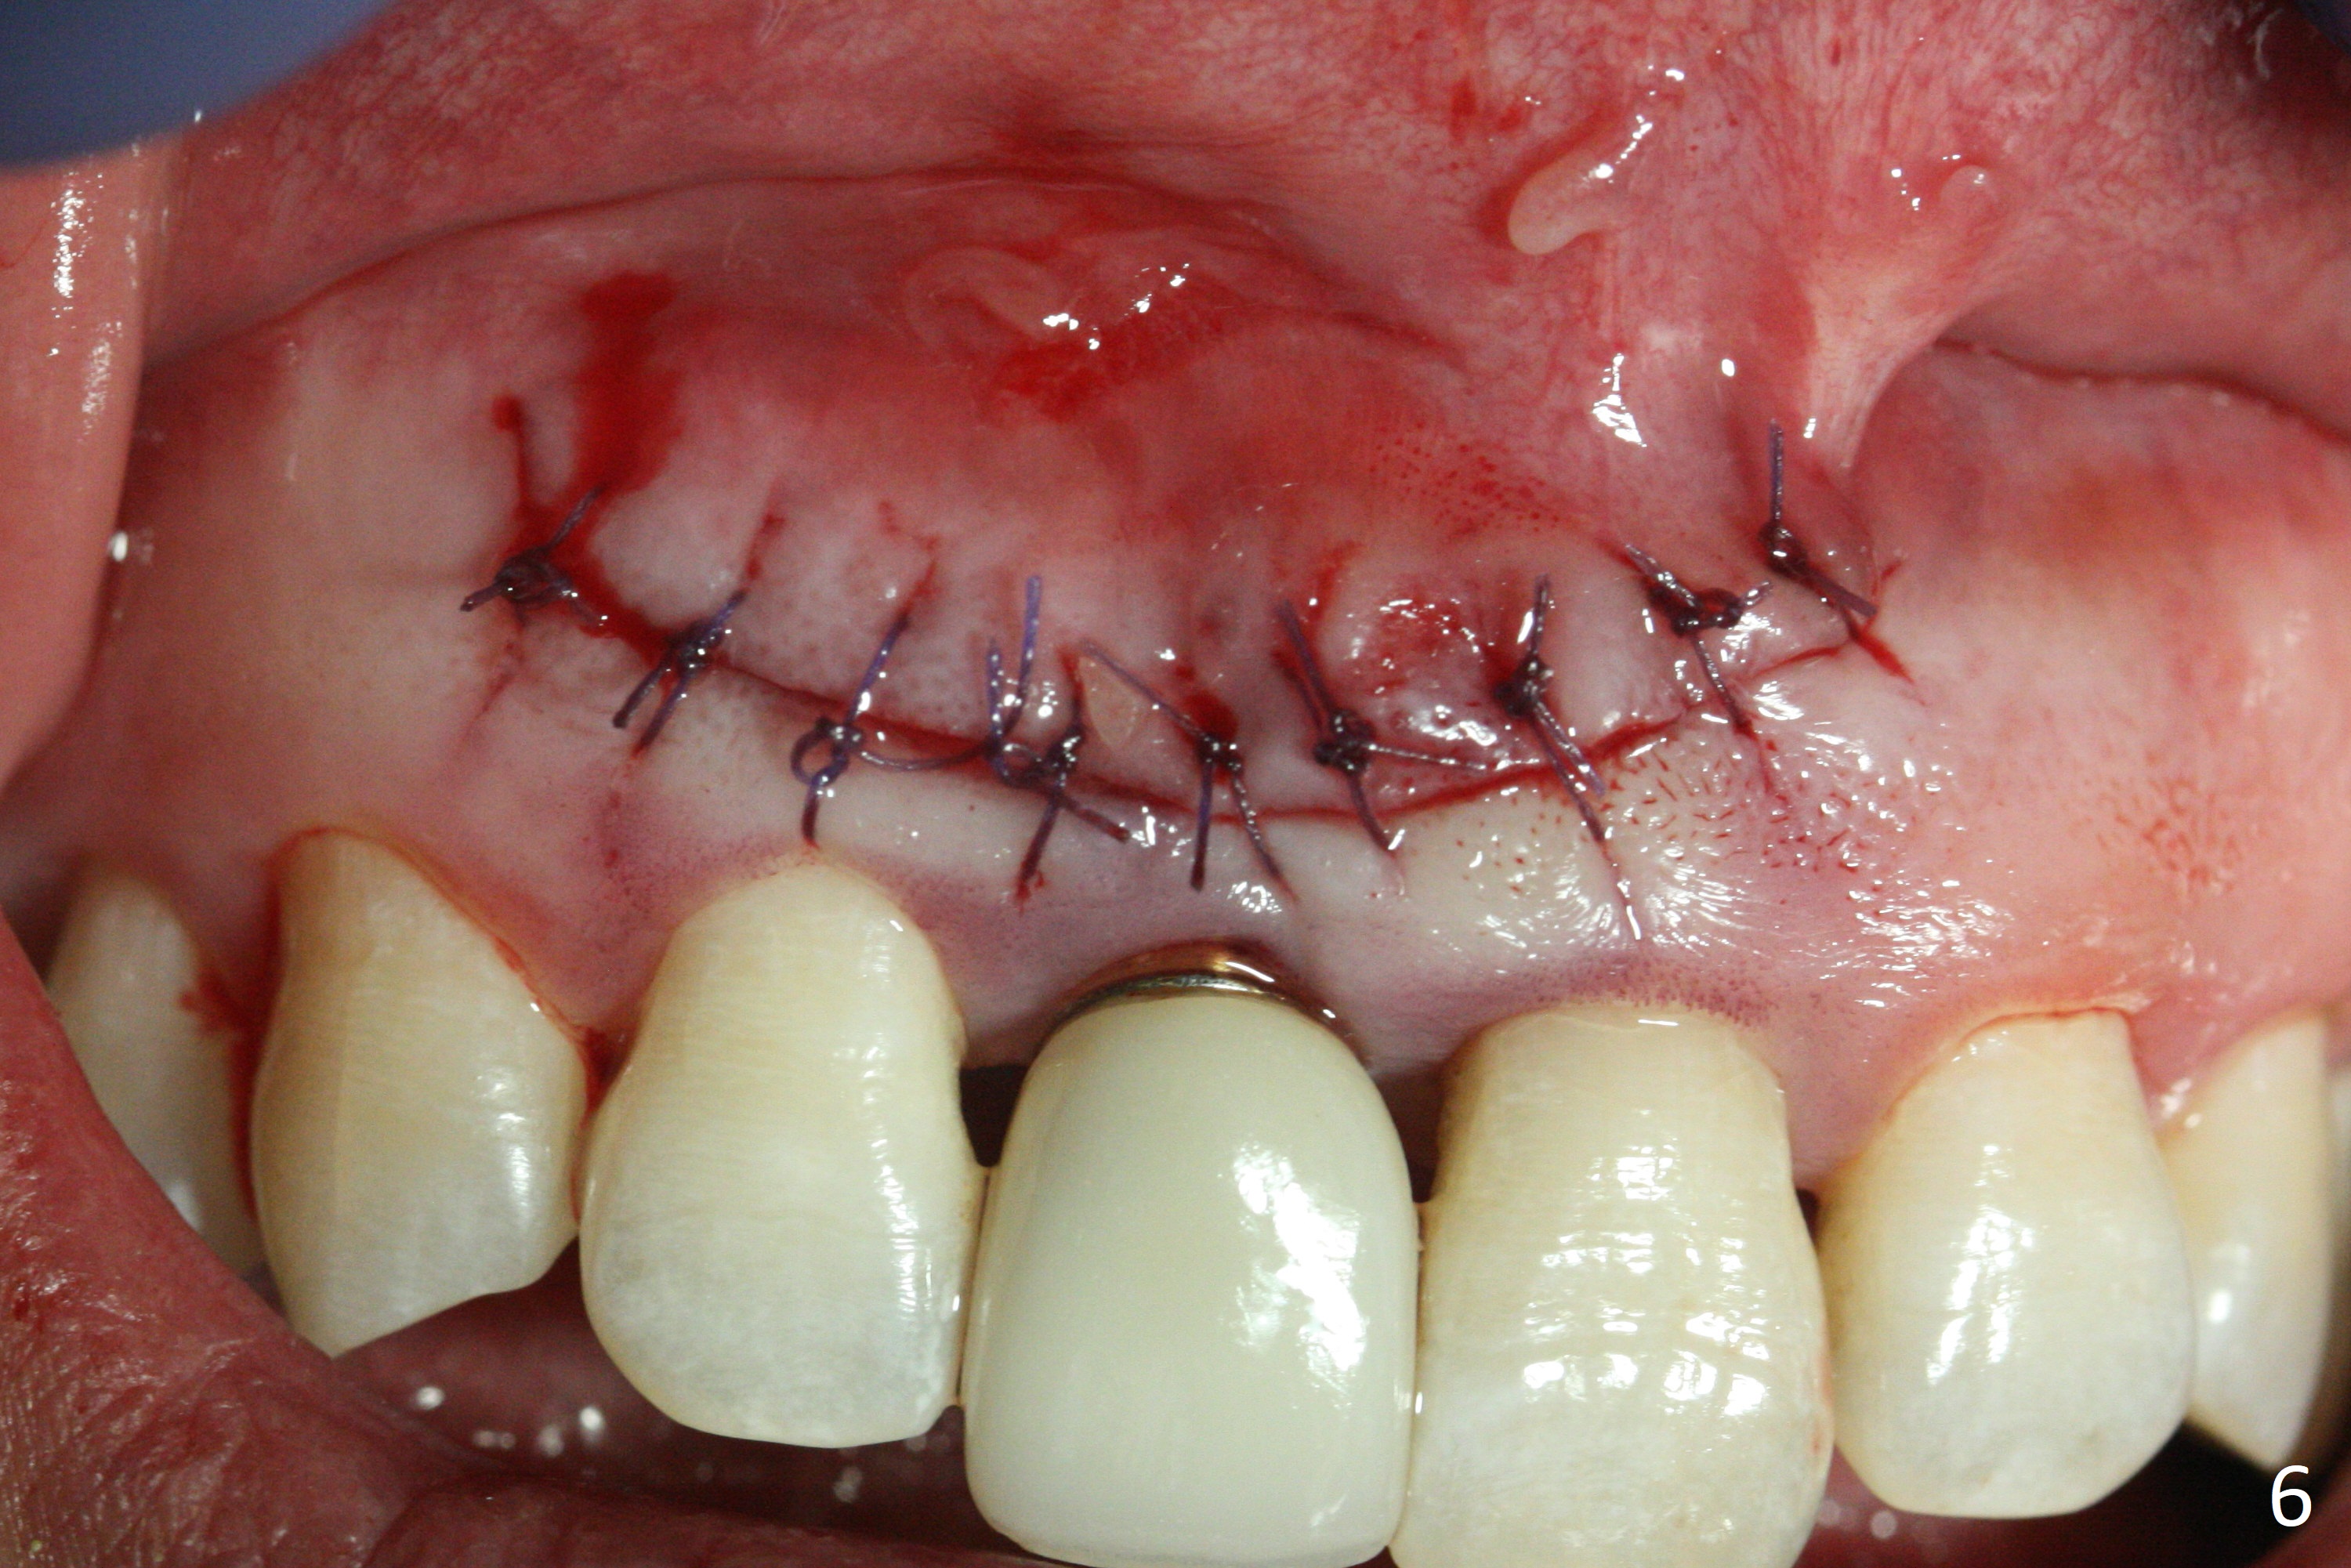

The patient returns because of purulent exudate from the buccal fistula (Fig.1 *) 1 year 9 months postop (1 year 3 months post cementation). Preop CT shows buccal thread exposure (Fig.2 arrowheads). To prevent postop gingival recession, a semilunar incision is made between the fistula and the gingival margin (Fig.3). After removal of granulation tissue (Fig.4), allograft in sticky bone form is packed (Fig.5). Following placement of PRF membrane and 6-month collagen membrane, the wound is closed (Fig.6). Since the implant (Fig.7 I) thread exposure is within bone (B) boundary (Fig.8 red dashed line), bone graft with PRF should be able to take care of periimplantitis (A: abutment). To prevent periimplantitis in similar situation, the immediate implant should be placed deep (not necessarily long, 18 mm) and narrower (3.5 mm instead of 3.8 mm). The defective buccal plate should be repaired with sticky bone and collagen membrane with incision if necessary. The wound does not dehisce 1 week postop (Fig.9) or 3 weeks postop (Fig.10, immediately post suture removal). Although bone graft seems to stay in place 6 months postop (Fig.11,12), the patient complains of bone graft expulsion sometimes. The buccal gingiva has deficiency (Fig.13). To fix it, make a remote incision (Fig.14 black line) and dissect before gingiva graft (Fig.15 dashed line). After removal of crown/abutment, the sinus track and implant surface are treated with Waterlase. A shorter cuff abutment is placed (4.5x5(4 to 3) mm) with a new provisional. The patient feels better with reduced sinus track 2 weeks postop (Fig.16).